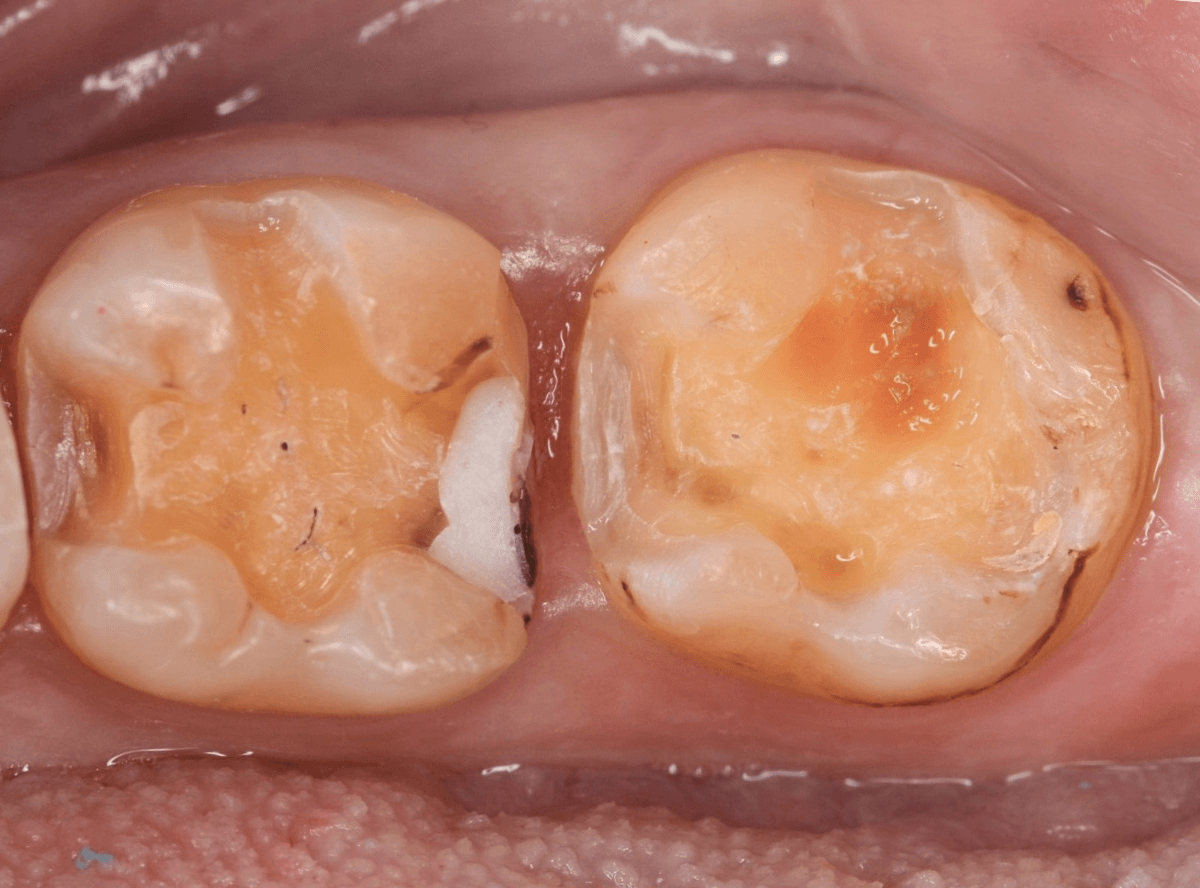

今回は、奥歯が神経に達する虫歯になってしまった患者さんのケースです。

隣りの歯とのすき間に大きな穴が空いているのが見えます。

レントゲン写真で確認します。

金属のつめものの下が、神経まで達する大きな虫歯になっています。

さて、神経の治療が終わり、歯の土台を作ったところで、手前の歯の側面にも虫歯が見つかり、治療を始めました。

手前の歯の虫歯も金属の中まで虫歯になっていました。

手前の歯の虫歯もかなり広い虫歯でした。